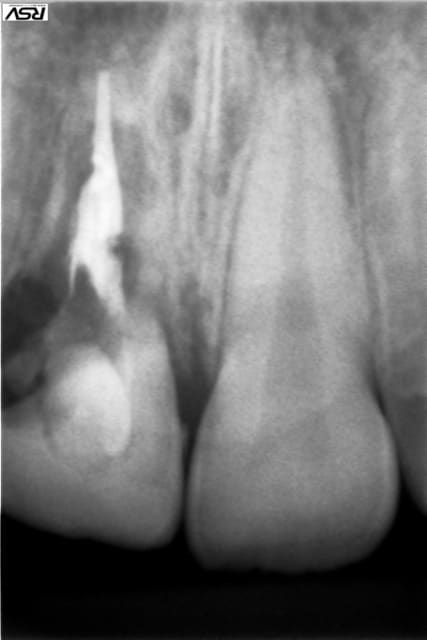

1° CAS une belle perf traitée avec du Biodentine. Résultat à 2 ans.

2°CAS expulsion - réimplantation immédiate - à 3 ans résorption interne - biodentine . le résultat est sans commentaire.

voilà les photos

1 hlkygf - Eugenol

2 jvxkl9 - Eugenol

3 owbzxu - Eugenol

6 alrbjd - Eugenol

3 iwmo8e - Eugenol

sur le cas avec le pivot qui transfixe, j'ai obturé d'abord avec la biodentine ,doucement au lentulo sous AL, j'ai laissé séché une semaine, et j'ai fait la reprise de traitement la semaine suivante , la dent était redevenue asymptomatique ( la patiente avait souffert tout le WE avec son pivot et sa provisoire, heureusement elle n'est pas allée voir un dentiste de garde...)